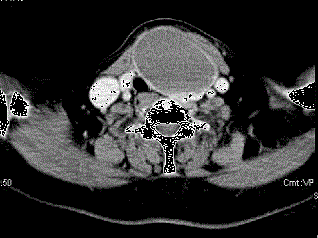

问题 女,56岁,发现颈部肿块一月余,CT如图所示,最可能诊断为 ( )

选项 A、甲状腺腺瘤 B、甲状腺脓肿 C、甲状腺乳头状癌 D、甲状腺原发淋巴瘤 E、甲状舌管囊肿

答案 A